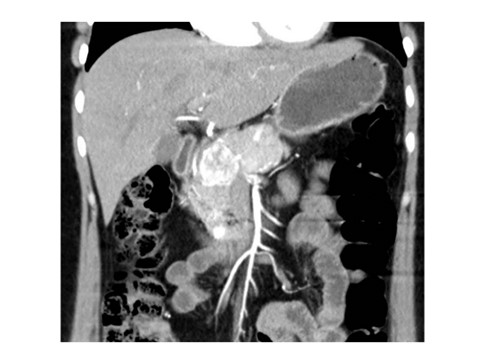

Caso 2

Paciente femenina de 48 años de edad que ingresa a Hospital Sanatorio Franchin por síntomas de cefalea y mareos, cuadro que se hace progresivo, presentando síncopes y posteriormente alteración del estado de conciencia. Los exámenes clínicos revelan una glucosa de 40 mg/dl, concomitante con insulina alta y péptido C elevado. Ingresa de forma programada para realización de duodeno pancreatectomía el 29 de mayo de 2021. Imágenes diagnósticas muestran estudio trifásico de tomografía de abdomen, lesión nodular en la cabeza del páncreas con ávido realce en fase arterial que en resonancia magnética se observa hiperintensa en T2, presenta restricción con la difusión y caída de la señal en el ADC. Además presenta realce tras la administración de contraste con gadolinio.

Estudio histopatológico reveló tumor neuroendocrino bien diferenciado grado 1.

Ahora bien, como se mencionaba al principio, el estudio ecográfico es de muy baja sensibilidad y se identifique o no la lesión por este estudio, nuestro siguiente paso en el algoritmo diagnóstico de esta lesión es la tomografía. Esta es la prueba no invasiva inicial, con una sensibilidad del 63% al 83%, y detecta del 70% al 80% de los tumores. Esta debe realizarse como un estudio trifásico: fase arterial temprana a los 30 segundos, fase venosa a los 70 segundos, fase tardía de 3 a 5 minutos. La característica de estos tumores por tomografía es que se presentan como una masa sólida que tiene un ávido realce en la fase arterial, cuyo realce se mantiene y se observa más tenue en la fase venosa y en los tiempos tardíos la lesión se homogeniza.

La resonancia magnética es el otro estudio de imagen no invasivo que nos permite la detección de la lesión con una sensibilidad mayor que la de la tomografía, del 85% al 95%, donde los insulinomas presentan un realce tras la administración de contraste con gadolinio y secuencias T1 sin contraste son lesiones hipointensas y en secuencias T2 son hiperintensas.

Para mi caso, y dando una visión general de los métodos de imagen no invasivos en esta revisión retrospectiva, solo a uno de los pacientes se le detectó la lesión por ecografía, donde se visualizó una lesión nodular hipoecogénica en el cuerpo del páncreas. A los demás pacientes se les detectó la lesión por tomografía en estudio trifásico, donde resaltan las características ya descritas por la literatura de lesiones hipervasculares con intenso realce en fase arterial, localizadas en diferentes partes del páncreas, como cabeza, cuerpo y cola.

La resonancia magnética confirmó aún más el diagnóstico de las lesiones ya previamente visualizadas en tomografía en esta revisión, con realce de las lesiones en secuencias T1 y contraste con gadolinio, y en las secuencias funcionales con restricción de la lesión y caída de la señal en el mapa de ADC.